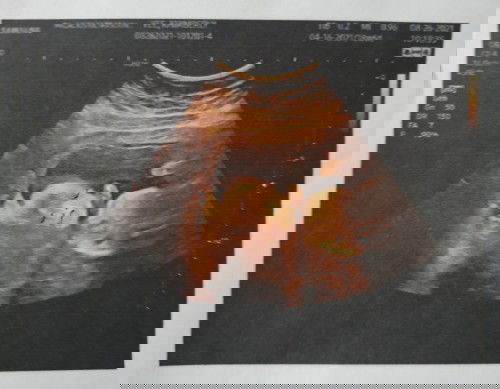

Hi 1st time mom here 18w 6d footling breech c baby, may tendency pa bang mging cephalic si baby?????